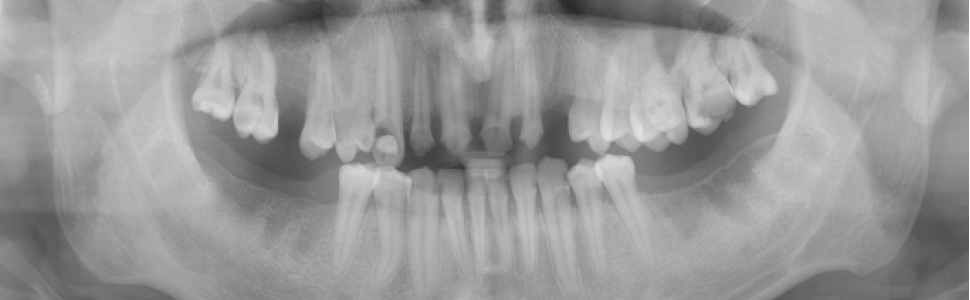

Martwicze zapalenie przyzębia z wydzieleniem martwaka kostnego – opis przypadku

Martwicze zapalenie przyzębia jest jednostką chorobową, w której dochodzi do rozwoju ostrego stanu zapalnego, martwicy przyzębia i szybkiej destrukcji struktur otaczających ząb. Niewłaściwie zdiagnozowana i leczona może prowadzić do poważnych powikłań, takich jak utrata zębów, wymaga zatem specjalistycznego podejścia terapeutycznego.

Necrotizing periodontitis is a disease which is characterized by the development of acute inflammation, necrosis of periodontium and rapid destruction of the structures surrounding the tooth. Diagnosed and treated incorrectly can lead to serious complications like the loss of teeth, so it requires a specialized therapeutic approach.